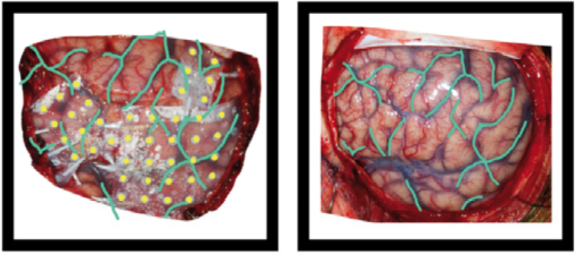

Example of the operative photo of ECoG electrodes (here is an annotated example in which electrodes and vasculature are marked, taken from Hermes et al., JNeuroMeth 2010).

Below is an example of a volume rendering of the cortical surface with a superimposed subdural electrode implantation. This map is often provided by the

EEG technician and provided to the epileptologists (for example, see Burneo JG et al. 2014. doi:10.1016/j.clineuro.2014.03.020).

sub-0002_ses-01_acq-render_photo.jpg